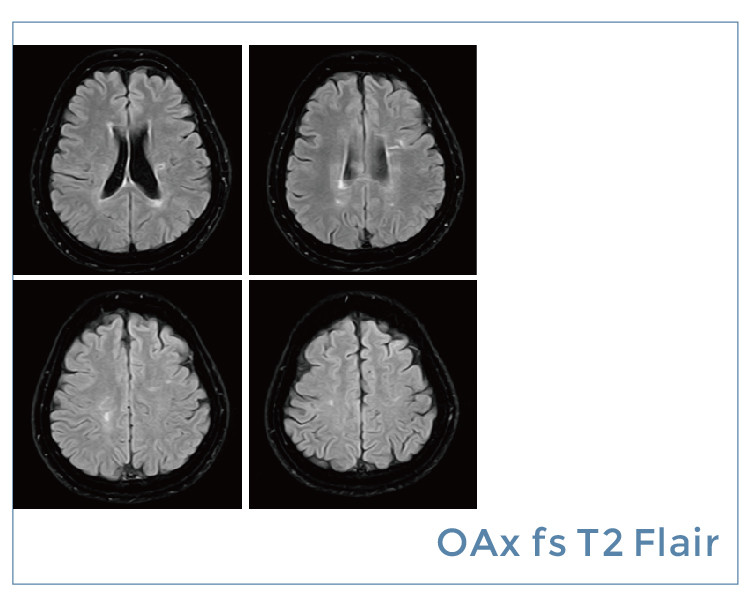

【朗润影像档案】磁共振影像病例分享(编号20190823)